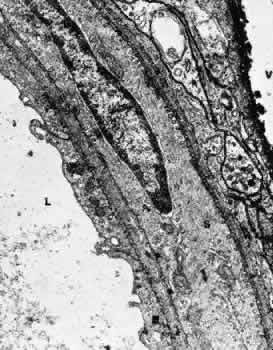

The iris blood vessels derive from the major iridic arterial circle and drain into the vortex system. The blood vessels of the iris are believed to have a slight corkscrew shape so they can accommodate to the changes in the length of the iris during dilation and contraction. A striking finding in all the iris vessels is the presence of thick collagenous adventitia that is several microns thick. There are approximately 200 radial vessels in the iris. The density of these vessels is greater than expected for the nutrition of the iris, and they probably account for anterior-segment thermal homeostasis and provide a high oxygen content for the corneal endothelium. Most of the vessels in the iris stoma are arterioles (Figs. 18, 19, and 20), venules, and capillaries (Fig. 21). The capillaries have unfenestrated endothelium with tight junctions. The main branches of these radial vessels form an incomplete circular arterial ring at the collarette (minor iris circle). Branches from the minor circle extend into the pupillary region to form capillary arcades. The venous drainage system parallels the arterial inflow pattern. The radial arteries of the iris are truly arterioles, with an overall diameter of 15 to 50 μm. The radial iridial veins are technically pericytic venules. They are approximately 30 to 90 μm in diameter. The media consists of one or two layers of pericytes. These cells make frequent contact with the endothelial cells but not with each other.

Fig. 18. Electron micrograph of a human iridial arteriole. The endothelial cell (E) is richly supplied with cellular organelles. In some areas (arrow), the smooth muscle cells (S) are in close contact with the endothelial cells.

Fig. 19. Electron micrograph of a human iridial arteriole from an older patient. Debris may be seen in the basement membrane surrounding the smooth muscle cells (arrows).

Fig. 20. Electron micrograph of a precapillary arteriole from a human iris in the region of the constrictor muscle. An incomplete layer of smooth muscle cells containing dense bodies (arrows) is present.